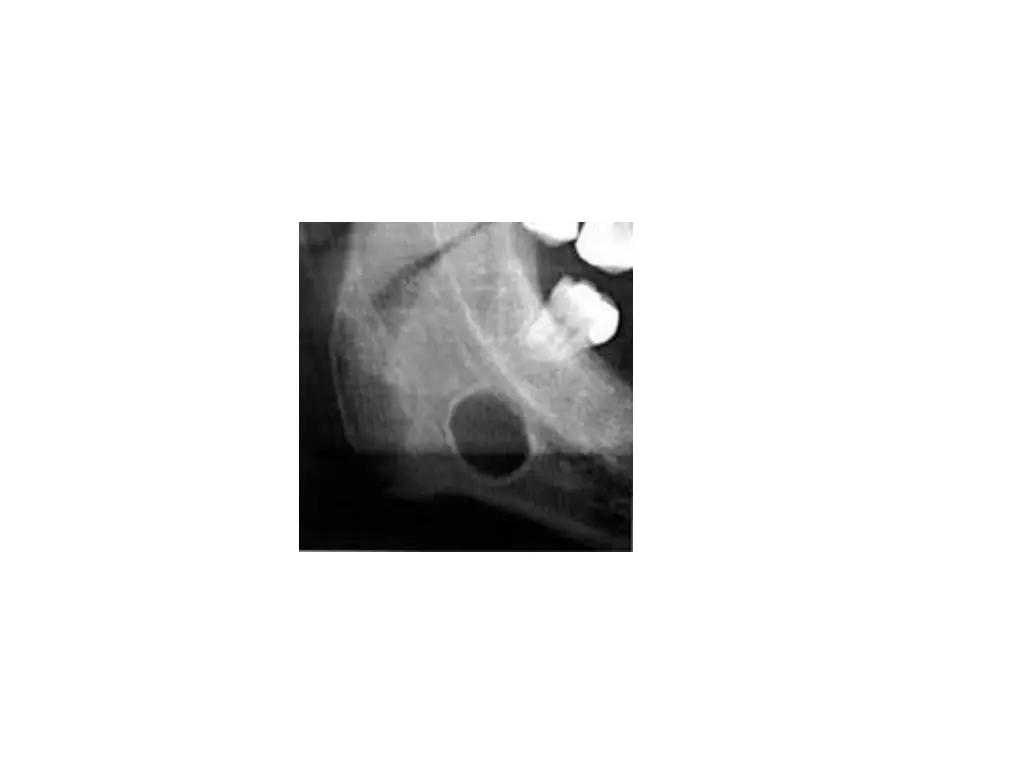

Aberrant salivary glands are salivary tissues that develop at unusual anatomic sites Locations for aberrant glands are middle ear cleft, EAC, neck, posterior mandible, anterior mandible, pituitary and cerebellopontine angle Stafne s cyst: located b/w angle and first molar below the level of inferior alveolar nerve Gland is usually asymptomatic and appears as a round radiolucency Less commonly anterior lingual submandibular salivary glands have been reported Aberrant glands: anterior mandible, appearing as r lucency at tooth apex, extraction sites, b/w roots